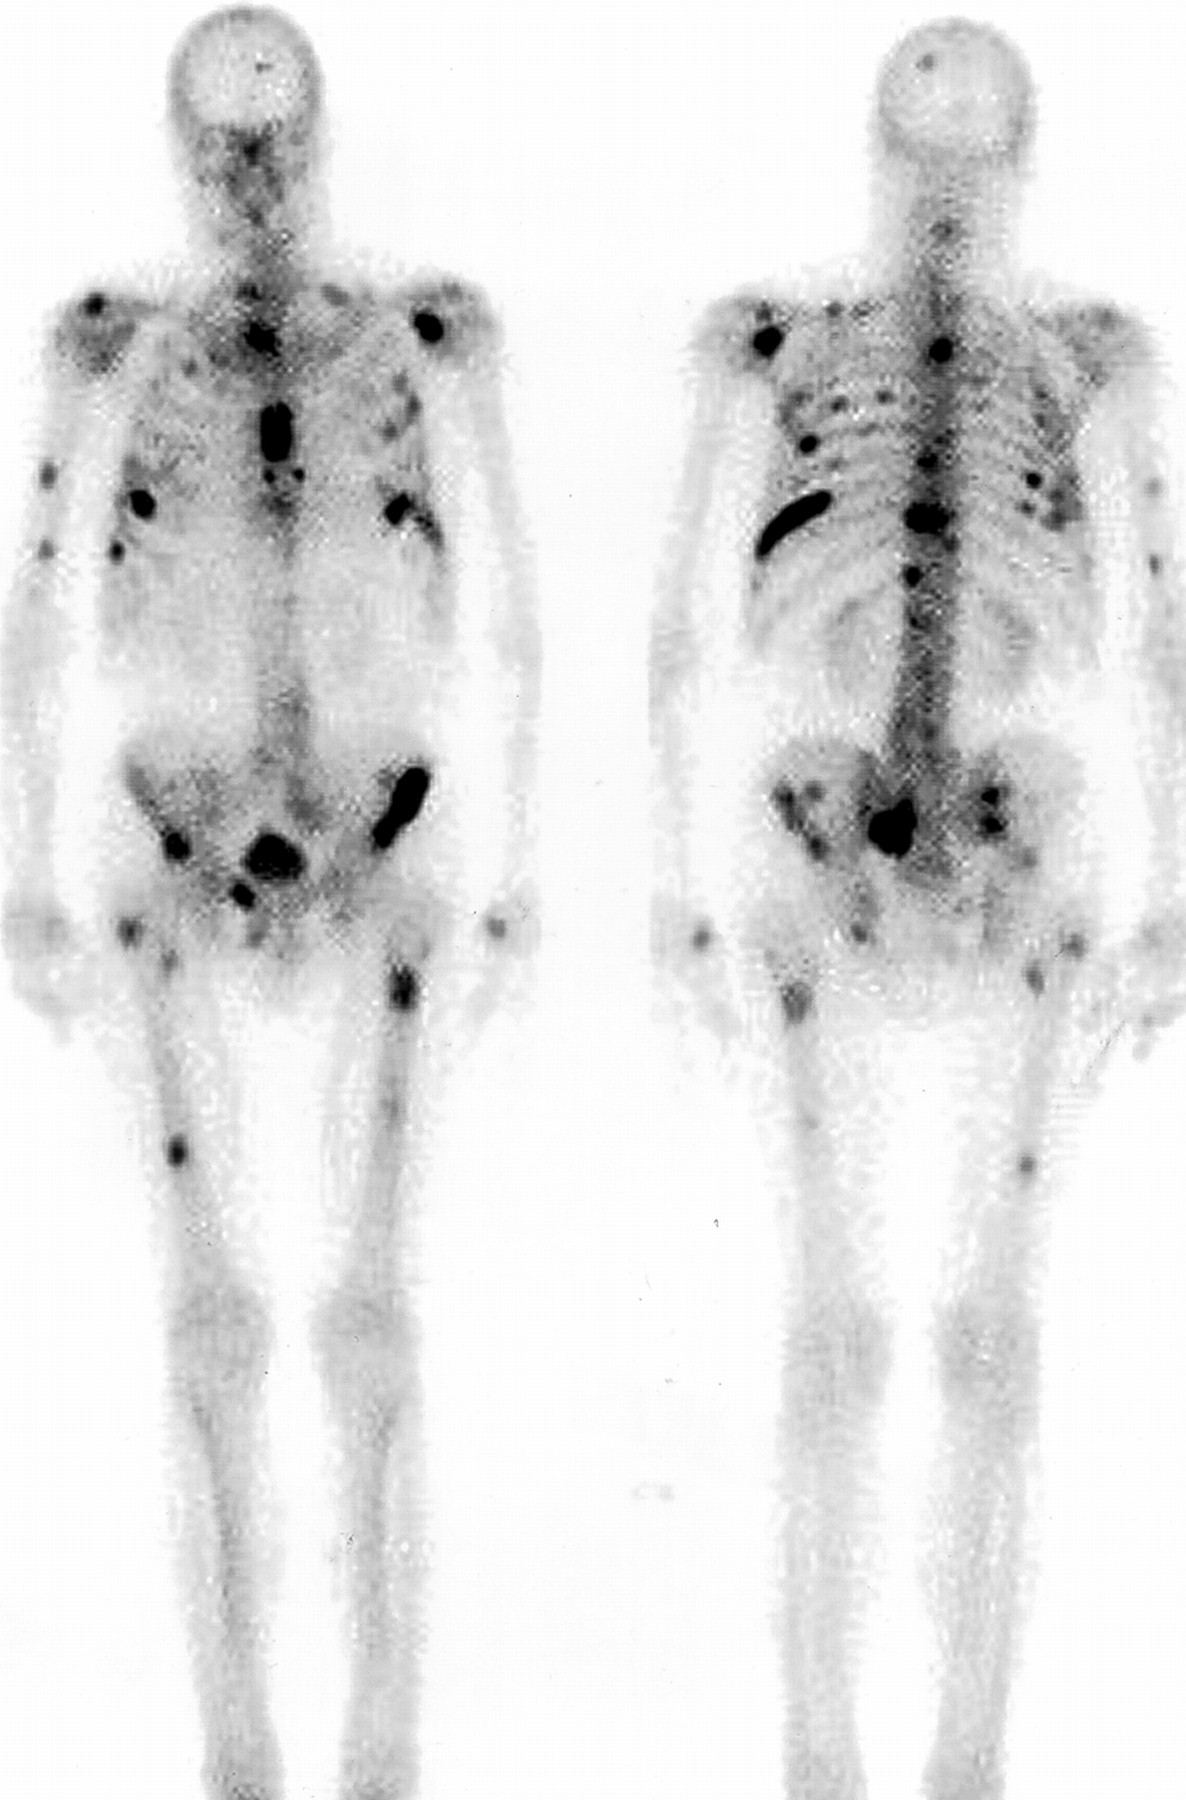

Radionuclide Imaging

Radionuclide imaging uses radioactivity to create images of physiological activity.